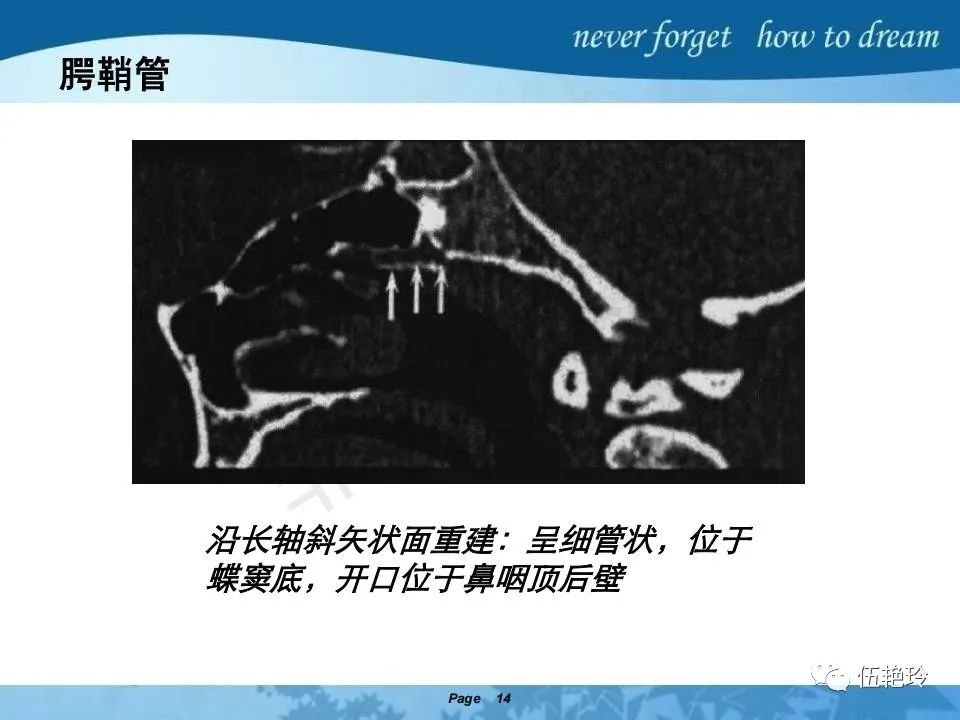

翼腭窝的解剖结构与鼻咽癌侵犯

2.31 向上颅内:①鼻咽顶壁→破裂孔(岩尖、斜坡)→蝶窦、海绵窦;②鼻咽顶壁→蝶骨基底部→蝶窦、海绵窦;③鼻咽侧壁→茎突前间隙→蝶骨大翼(卵圆孔)→海绵窦;④鼻咽侧壁→茎突前间隙→翼腭窝→ 颞下窝;⑤鼻咽前壁→鼻腔→翼突、翼腭窝→眶下裂→眶尖→海绵窦;⑥鼻咽前壁→鼻腔→上颌窦、筛窦;